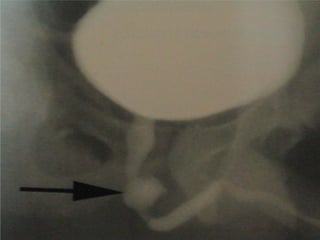

Tension pneumothorax

High pressure pneumothorax causing

cardiovascular compromised status

* chest injury

* dyspnea & tachypnea

* distended neck vein

* deviated trachea

* hypotension

* tympanic on percussion

* absent breath sound